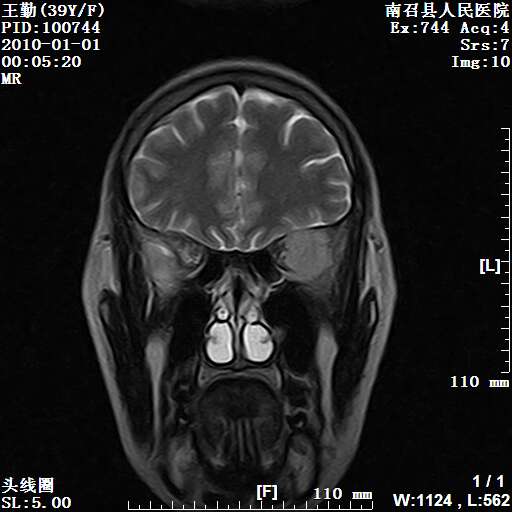

以下是引用随光逐影在2010-1-22 9:03:00的发言:[br]考虑左侧中颅窝(蝶骨翼区)脑膜瘤侵犯蝶骨翼并突入左侧眼眶。

以下是引用水过无痕在2010-1-22 14:55:00的发言:[br]一、定位:颅外占位;二、定性:恶性可能性大;三、组织来源:来源于左侧眼外直肌或其他部位;考虑为:横纹肌肉瘤>转移瘤>脑膜瘤.